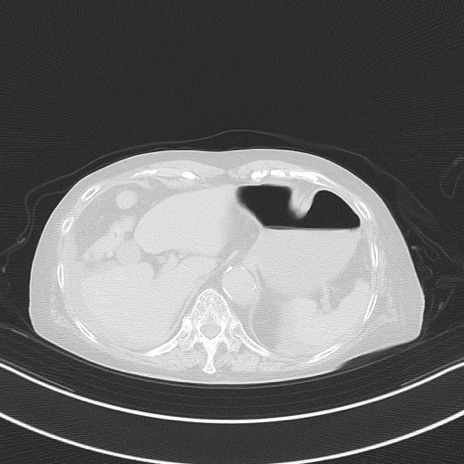

横断像

他院CT